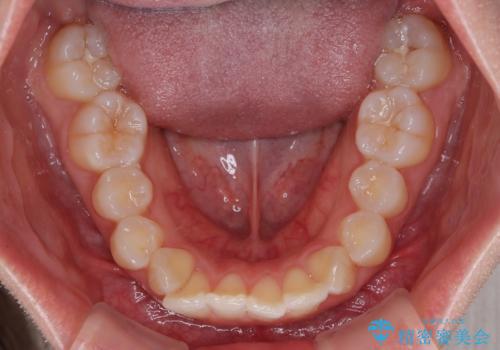

- 上の前歯の隙間を気にして来院された患者様です。

インビザラインにより、上下の歯列を側方に拡大しつつ、前歯の隙間を閉じていくこととしました。

隙間の原因は強い咬合力や舌の突出癖、小帯の異常付着などがありますが、舌のトレーニングをしっかりと行いながら、装着時間を遵守して装着していただいたおかげで、スムーズに治療を終えることができました。